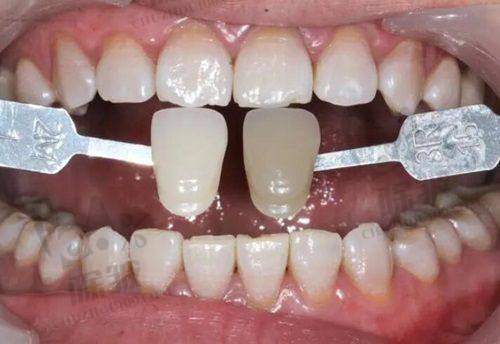

普宁金铂利口腔近期更新了收费标准,旨在为患者提供更加透明和优质的服务。以下是该机构目前开展的详细项目价格表:瓷贴面2790元起,种植牙3280元起,牙齿镶嵌1200元起,牙齿矫正8800元起,根管治疗800元起,超声波洁牙200元起,拔牙(普通)180元起,拔牙(智齿)400元起,牙周治疗500元起,儿童窝沟封闭150元起。